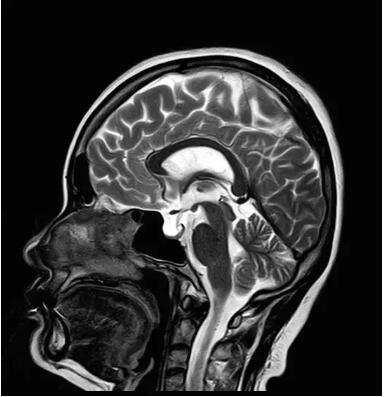

佳能磁共振推出了全新一代Vantage Elan1.5T磁共振,這款日本原裝進(jìn)口的 1.5T磁共振,集當(dāng)今磁共振創(chuàng)新科技成果于一身:

高精度鍍膜新磁體——鍍膜貼合技術(shù) 獲得最佳磁場(chǎng)均勻度

3DRSCE微雕梯度 ——精準(zhǔn)控制頻率和相位輸出理想波形

Pure 射頻影像鏈——圖像信噪比提升40%

“螢火蟲”成像技術(shù)——見所未見 微小腫瘤無(wú)處遁藏